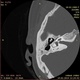

28 лет. ЛОР пишет правосторонний хронический средний отит. Перфорация барабанной перепонки, отделяемое из уха.

Мое скромное мнение такое: Пневматизация сосцевидных отростков слабо выражена с обеих сторон, справа ячейки частично заполнены содержимым патологической плотности(мягкотканной). Внутреннее ухо с обеих сторон без патологии. Наружный слуховой проход, барабанные полости, костные части слуховых труб с обеих сторон без нарушения пневматизации. Слуховые косточки хорошо определяются(??) без патологичесих изменений(. ).

На снимках стрелками - это, если я правильно понимаю, склерозированные и утолщенные части разрушенной барабанной перепонки? Это все что мне показалось патологичным в ушах.

Что могу, но коротко. В основном склеротический тип строения обоих сосцевидных отростков - это уже ненорма, имеются патологические потности в сохранившихся ячейках правого сосцевидного отростка, пневматизация в ячейках левого отростка сохранена. Патологических плотностей в барабанных полостях и антральных клетках не выявлено. Размеры полостей среднего уха - без особенностей. Слуховые косточки прослеживаются. Деструкций не выявлено. Костные устья слуховых труб - без признаков обстукции. Состояние барабанных перепонок оценивать пока не научился. Состояние внутренних ушей (ухов) - без особенностей. В принципе все укладывается в правосторонний средний отит.